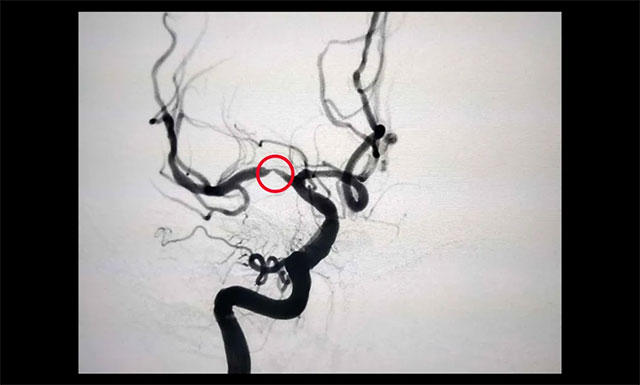

▲ 患者右側大腦中動脈M1段重度狹窄

經(jīng)行 DSA 檢查,胡老伯右側椎動脈纖細,右側大腦中動脈 M1 段重度狹窄(約80%-90%),只剩下不到20%的空間,血流明顯受阻。李振并主任表示,大腦中動脈是頸內(nèi)動脈的延續(xù),它供應大腦外側面3/4的血液,所以大腦中動脈狹窄后會導致部分區(qū)域血流不足而引起相關癥狀。嚴重時會出現(xiàn)偏身運動障礙、偏身感覺障礙,甚至昏迷。一般情況下,當大腦中動脈狹窄程度超過70%,需要及時進行支架植入治療,同時要注意其他危險因素的預防。